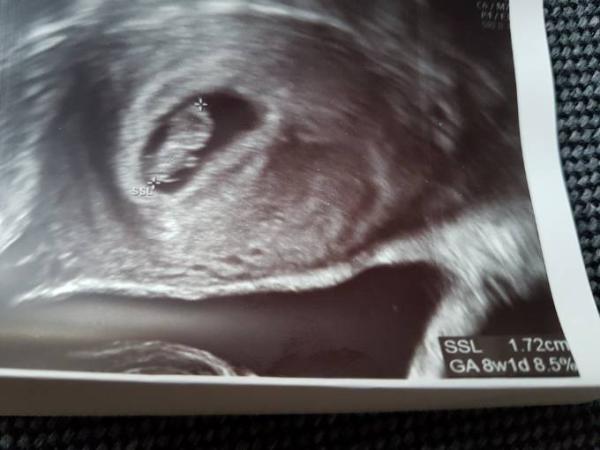

Also, da ich Blutungen habe, die vom hämatom kommen, bin ich immer sofort ins kh wenn es rot war (Wochenende, Feiertage). Am Montag war ich dort das letzte mal. Könnt euch ja die Messung im Bild ansehen. 1.72cm. Wurde da auf 8w1d zurückgestuft oder besser gesagt das Krümel. Quasi 4 Tage. Da gehe ich ja noch mit. Aber ganze 4 Tage später beim frauenarzt misst er 1,4cm und stuft mich somit glatte 11 Tage zurück insgesamt. So will er es auch in den mutterpass Einschreiben. Kann mir das doch nicht vorstellen, dass das mäusel geschrumpft sein soll. Und soviel zurück kann ich auch nicht sein.

Das Bild aus dem kh kann man doch ernst nehmen oder? Embryo ist ja schön gerade und die Punkte wurden auch gut gesetzt meiner Meinung nach.

Hallo, das Bild schaut sehr schön aus und die Punkte sind gut gesetzt meiner Meinung nach. Hattest du denn immer nen regelmäßigen Zyklus oder kann sich dein et verschoben haben? Mein fa sagte immer es kann leichte Abweichungen geben. 4 Tage finde ich nicht schlimm Sodas du dir Gedanken machen müsstest, 11 Tage und Baby geschrumpft finde ich persönlich unrealistisch.war das der selbe Arzt ? Ich denke das ist rein biologisch gar nicht möglich aber die Kinder liegen auch nicht immer gleich und bei einem minimalen abweichen der gesetzten Punkte macht es das in diesem Stadion eben viel aus. Sei nicht besorgt. Lg Tambelia

Hallo! Also ich wurde ganz am Anfang erstmal knapp 14 Tage zurück gestuft, man dachte aber zuerst es wäre ein Windei, bei einem Kontrolltermin stellte man das in der rechnerisch 10ten SSW einen Embryo im alter von 8 SSW fest, das hatte mit einem verzögerten ES zu tun. Bei dem US damals gabs verschiede Bilder ich bekommen habe und auf jedem einzelnen gab es bei der SSL Messung leichte Abweichungen, jeh nachdem wie gut er den Krümel erwischt hatte. Hast du denn ein Bild von der zweiten Messung erhalten? Ich finde das Bild das du gepostet hast ein sehr gutes Bild, so ähnlich war eines meiner Bilder auch das der Doc dann auch zum neu berechne des ET benutzt hat. Andere waren etwas verschwommer. Ich kenn mich jetzt nicht sonderlich gut mit US Geräten aus aber wenn so ein gravierender Unterschied besteht, könnte es vielleichg auch einfach sein das der Doc im Krankenhaus bessere Geräte hat und man es damit besser erkennt? Ihr konntet sicher schon einen Herzschlag bei beiden Untersuchungen sehen, oder? Das die Krümels schrumpfen hab ich jetzt auch noch nicht gehört!